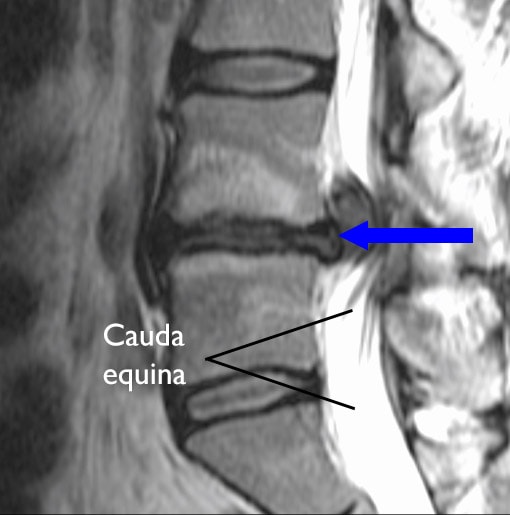

Herniated disk compressing cauda equina

In this MRI scan, a herniated disk (arrow) is compressing the cauda equina.